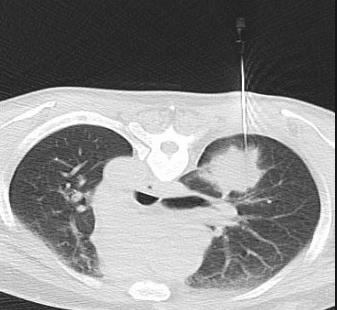

Tiến hành Gây tê quanh vùng da được khảo sát. Bác sĩ sẽ rạch một đường rất nhỏ trên da bằng lưỡi dao phẫu thuật, sau đó thực hiện chọc kim dẫn đường qua vị trí rạch da dưới sự hướng dẫn của cắt lớp vi tính đưa kim đến sát vị trí của tổn thương (khối u).

Kim sinh thiết chuyên dụng sẽ được đưa qua kim dẫn đường để tiếp cận khối u. Bác sĩ sẽ tiến hành sinh thiết cắt vào khối u, lấy 2-3 mẫu bệnh phẩm theo các hướng khác nhau. Vì khi người bệnh thở khối u sẽ di chuyển theo nhịp thở nên người bệnh cần cố gắng nín thở trong lúc kim chọc qua màng phổi, nhu mô phổi và khi sinh thiết.

Ê-kíp tiến hành chụp một số lớp cắt qua vùng sinh thiết để kiểm tra người bệnh có bị các tình trạng như chảy máu phổi, màng phổi, tràn khí màng phổi,...hay không.